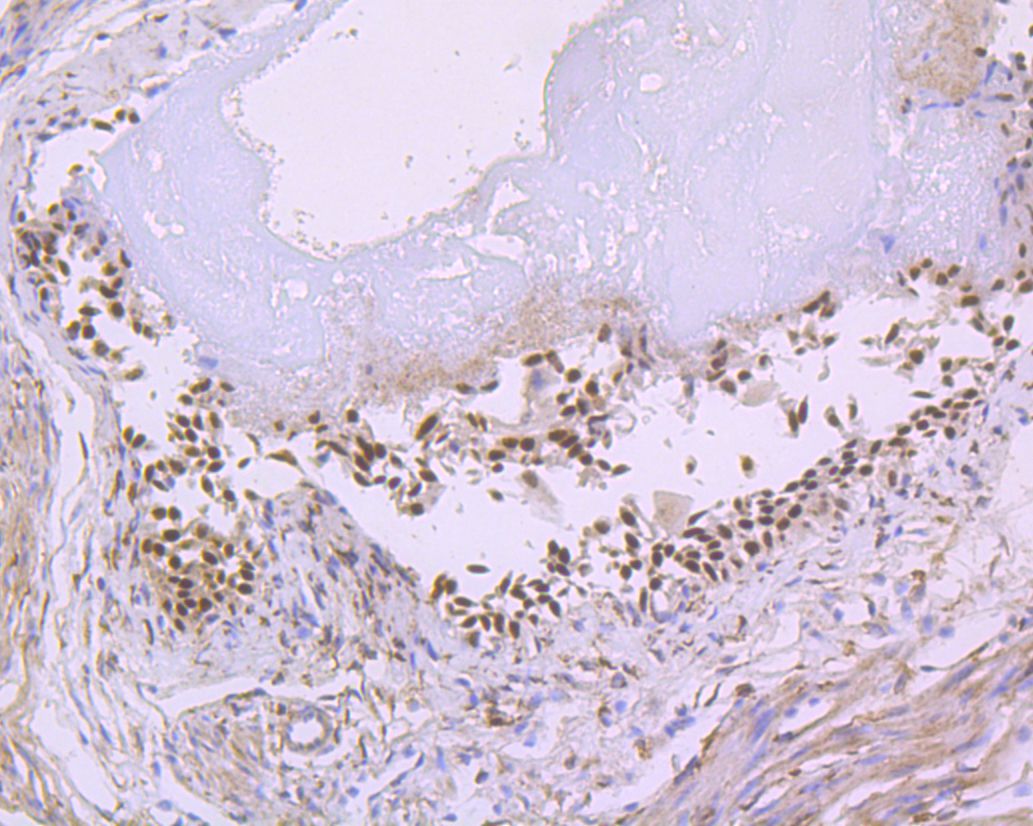

Catalog# ET7110-47

p63 Recombinant Rabbit Monoclonal Antibody [JE53-53]

IHC-P

Human

-